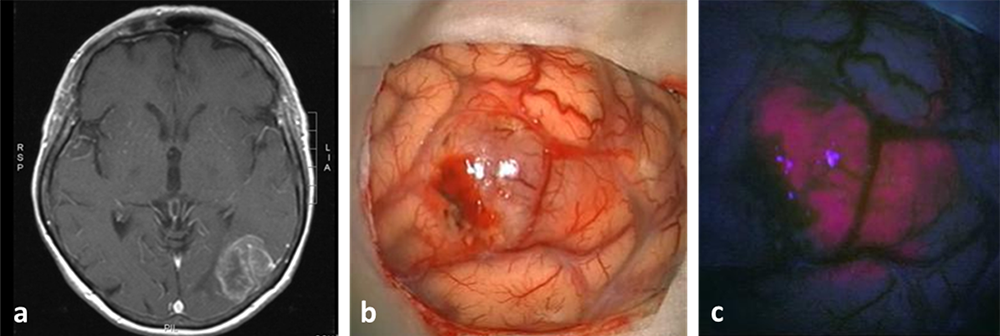

Durch Verabreichung eines Tracers, welcher sich selektiv in unterschiedlichem Ausmaß in bestimmte Hirntumorzellen einlagert und unter dem Operationsmikroskop im Fluoreszenzlicht aufleuchtet, können der Tumor und dessen Grenzen zum benachbarten Gehirn während der Operation dargestellt und die Operationsstrategie dem Ziel der größtmöglichen funktionserhaltenden Tumorresektion folgend adaptiert werden.

Abbildung 3